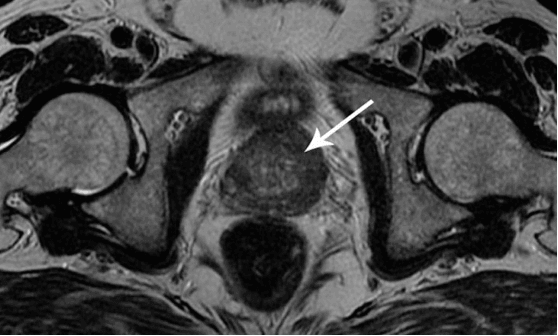

+ Voir les photos (18+)

interesting image

Cancer de la prostate chez un homme de 58 ans.